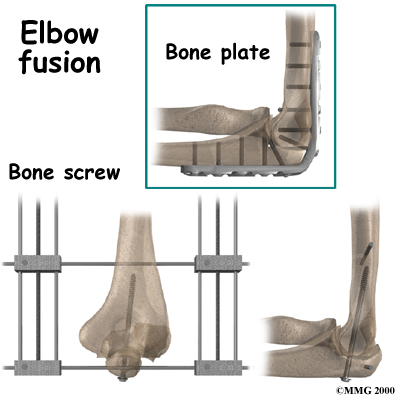

Elbow Fusion

A fusion surgery (also called arthrodesis) eliminates pain by making the bones of the joint grow together, or fuse, into one solid bone. Fusions were very common before the invention of artificial joints. Even today, joint fusions are commonly used in many different joints to get rid of the pain of arthritis.

A fusion surgery (also called arthrodesis) eliminates pain by making the bones of the joint grow together, or fuse, into one solid bone. Fusions were very common before the invention of artificial joints. Even today, joint fusions are commonly used in many different joints to get rid of the pain of arthritis.

An elbow fusion will greatly decrease the motion in your arm however, it does leave you with a strong and pain-free elbow. People who need a good range of motion in their elbow should consider another type of operation, such as an elbow joint replacement.